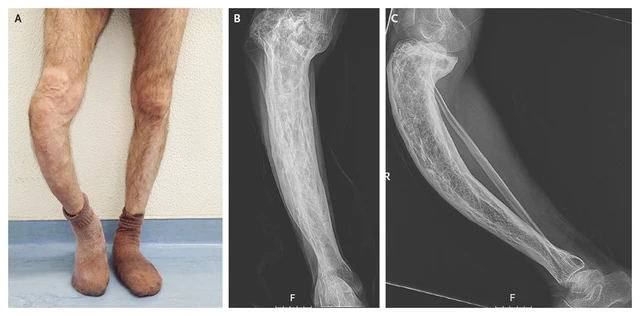

Bệnh Paget xương là rối loạn mạn tính ảnh hưởng đến quá trình tái tạo xương, làm cho xương phát triển không đều và yếu đi. Thường xuất hiện ở xương chậu, đầu, cột sống, và chi dưới. Do xương tái phục hồi quá nhanh nên dẫn tới xương to và mềm hơn bình thường, chúng có thể bị biến dạng và dễ bị gãy. Paget thường chỉ ảnh hưởng đến một hoặc một vài xương.